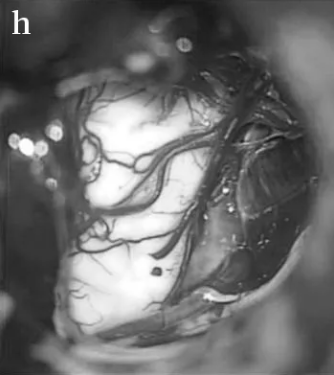

STEP 06:重建近端(k)和远端(l)神经残端(PS近端残端,DS远端残端)

STEP 07:准备合适长度的移植体(m), 并用纤维蛋白胶(n)固定到残端,脂肪用于防止脑脊液泄漏(o)。

随后,巴教授进行了面神经重建术,将2厘米长的腓肠神经移植桥接到健康的面神经内侧和外侧残端,对面神经功能进行重建。术后13天,Elsa得以恢复出院,无任何新发神经功能缺损,更没有出现面瘫、耳聋等严重后果。12个月后的随访检查显示,她的面神经明显恢复。从此,Elsa又可以重展笑容。